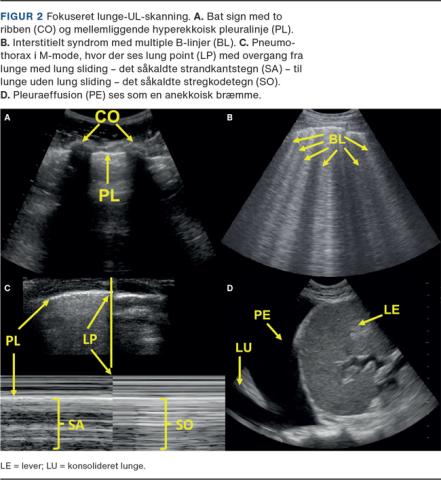

Fokuseret lunge-UL-skanning (FLUS) er en metode til diagnosticering af interstitielt syndrom (IS), pneumothorax, pleuraeffusion og anden åbenlys patologi. Ved FLUS skannes der ofte otte, men op til 14 zoner på thorax (Figur 1A). Den abdominale probe er en god allround probe til FLUS. Patienten kan skannes siddende eller liggende, blot man er opmærksom på, at positionen vil have betydning, da pneumothorax bedst erkendes med patienten liggende og pleuraeffusion med patienten siddende. Proben placeres på tværs af et interkostalrum, og et billede med to ribben og en mellemliggende hyperekkoisk linje, pleuralinjen, eftersøges (Figur 2A). Pleuralinjen repræsenterer de to pleurablade, der under respirationen glider mod hinanden og danner en horisontal bevægelse kaldet lung sliding.

Ved FLUS kan man erkende IS. Ved IS ses multiple B-linjer bilateralt i flere skanningszoner (Figur 2B). B-linjer er artefakter, der ses som hyperekkoiske vertikale linjer, der strækker sig fra pleuralinjen til bunden af billedet [4]. B-linjer er dynamiske strukturer, og de kan således ændres i antal og fordeling. IS kan ses ved diffust øget densitet af luftholdigt lungevæv, f.eks. ved lungeødem, interstitielle lungesygdomme og COVID-19. Fravær af IS kan også anvendes diagnostisk, f.eks. har FLUS en højere sensitivitet og specificitet ved diagnostik af kardiogent lungeødem end f.eks. røntgenoptagelse af thorax og pro-brain natriuretisk peptid [5].

FLUS har en højere præcision ved diagnostik af pneumothorax end f.eks. røntgenoptagelse af thorax [6]. Ved pneumothorax vil lung sliding og lungepuls være fraværende, da bevægelse af pleura viscerale kun kan erkendes, hvis der ikke er luft imellem de to pleurablade. Lungepuls er en bevægelse af pleuralinjen synkront med hjertefrekvensen, hvor hjertets kontraktionen skubber til det nærliggende lungevæv [7]. Manglende lung sliding og lungepuls kan dog også forekomme ved en række andre tilstande, f.eks. ved hhv. pleurodese og intubation af kontralaterale hovedbronchus [4]. Diagnostisk for pneumothorax er et område, hvor man ser en overgang fra manglende lung sliding til bevaret lung sliding kaldet lung point (Figur 2C).

Pleuraeffusion kan erkendes på FLUS som en anekkoisk bræmme (Figur 2D) med større præcision end ved røntgenoptagelse [8]. FLUS kan ikke med sikkerhed anvendes til afklaring af årsagen til en pleuraeffusion. Ved en væskebræmme på over 2 cm hos en akut medicinsk patient bør der derfor som udgangspunkt foretages akut punktur [9]. Størrelse og klinik vil være afgørende for, om denne skal foretages med anlæggelse af et kateter eller ej.